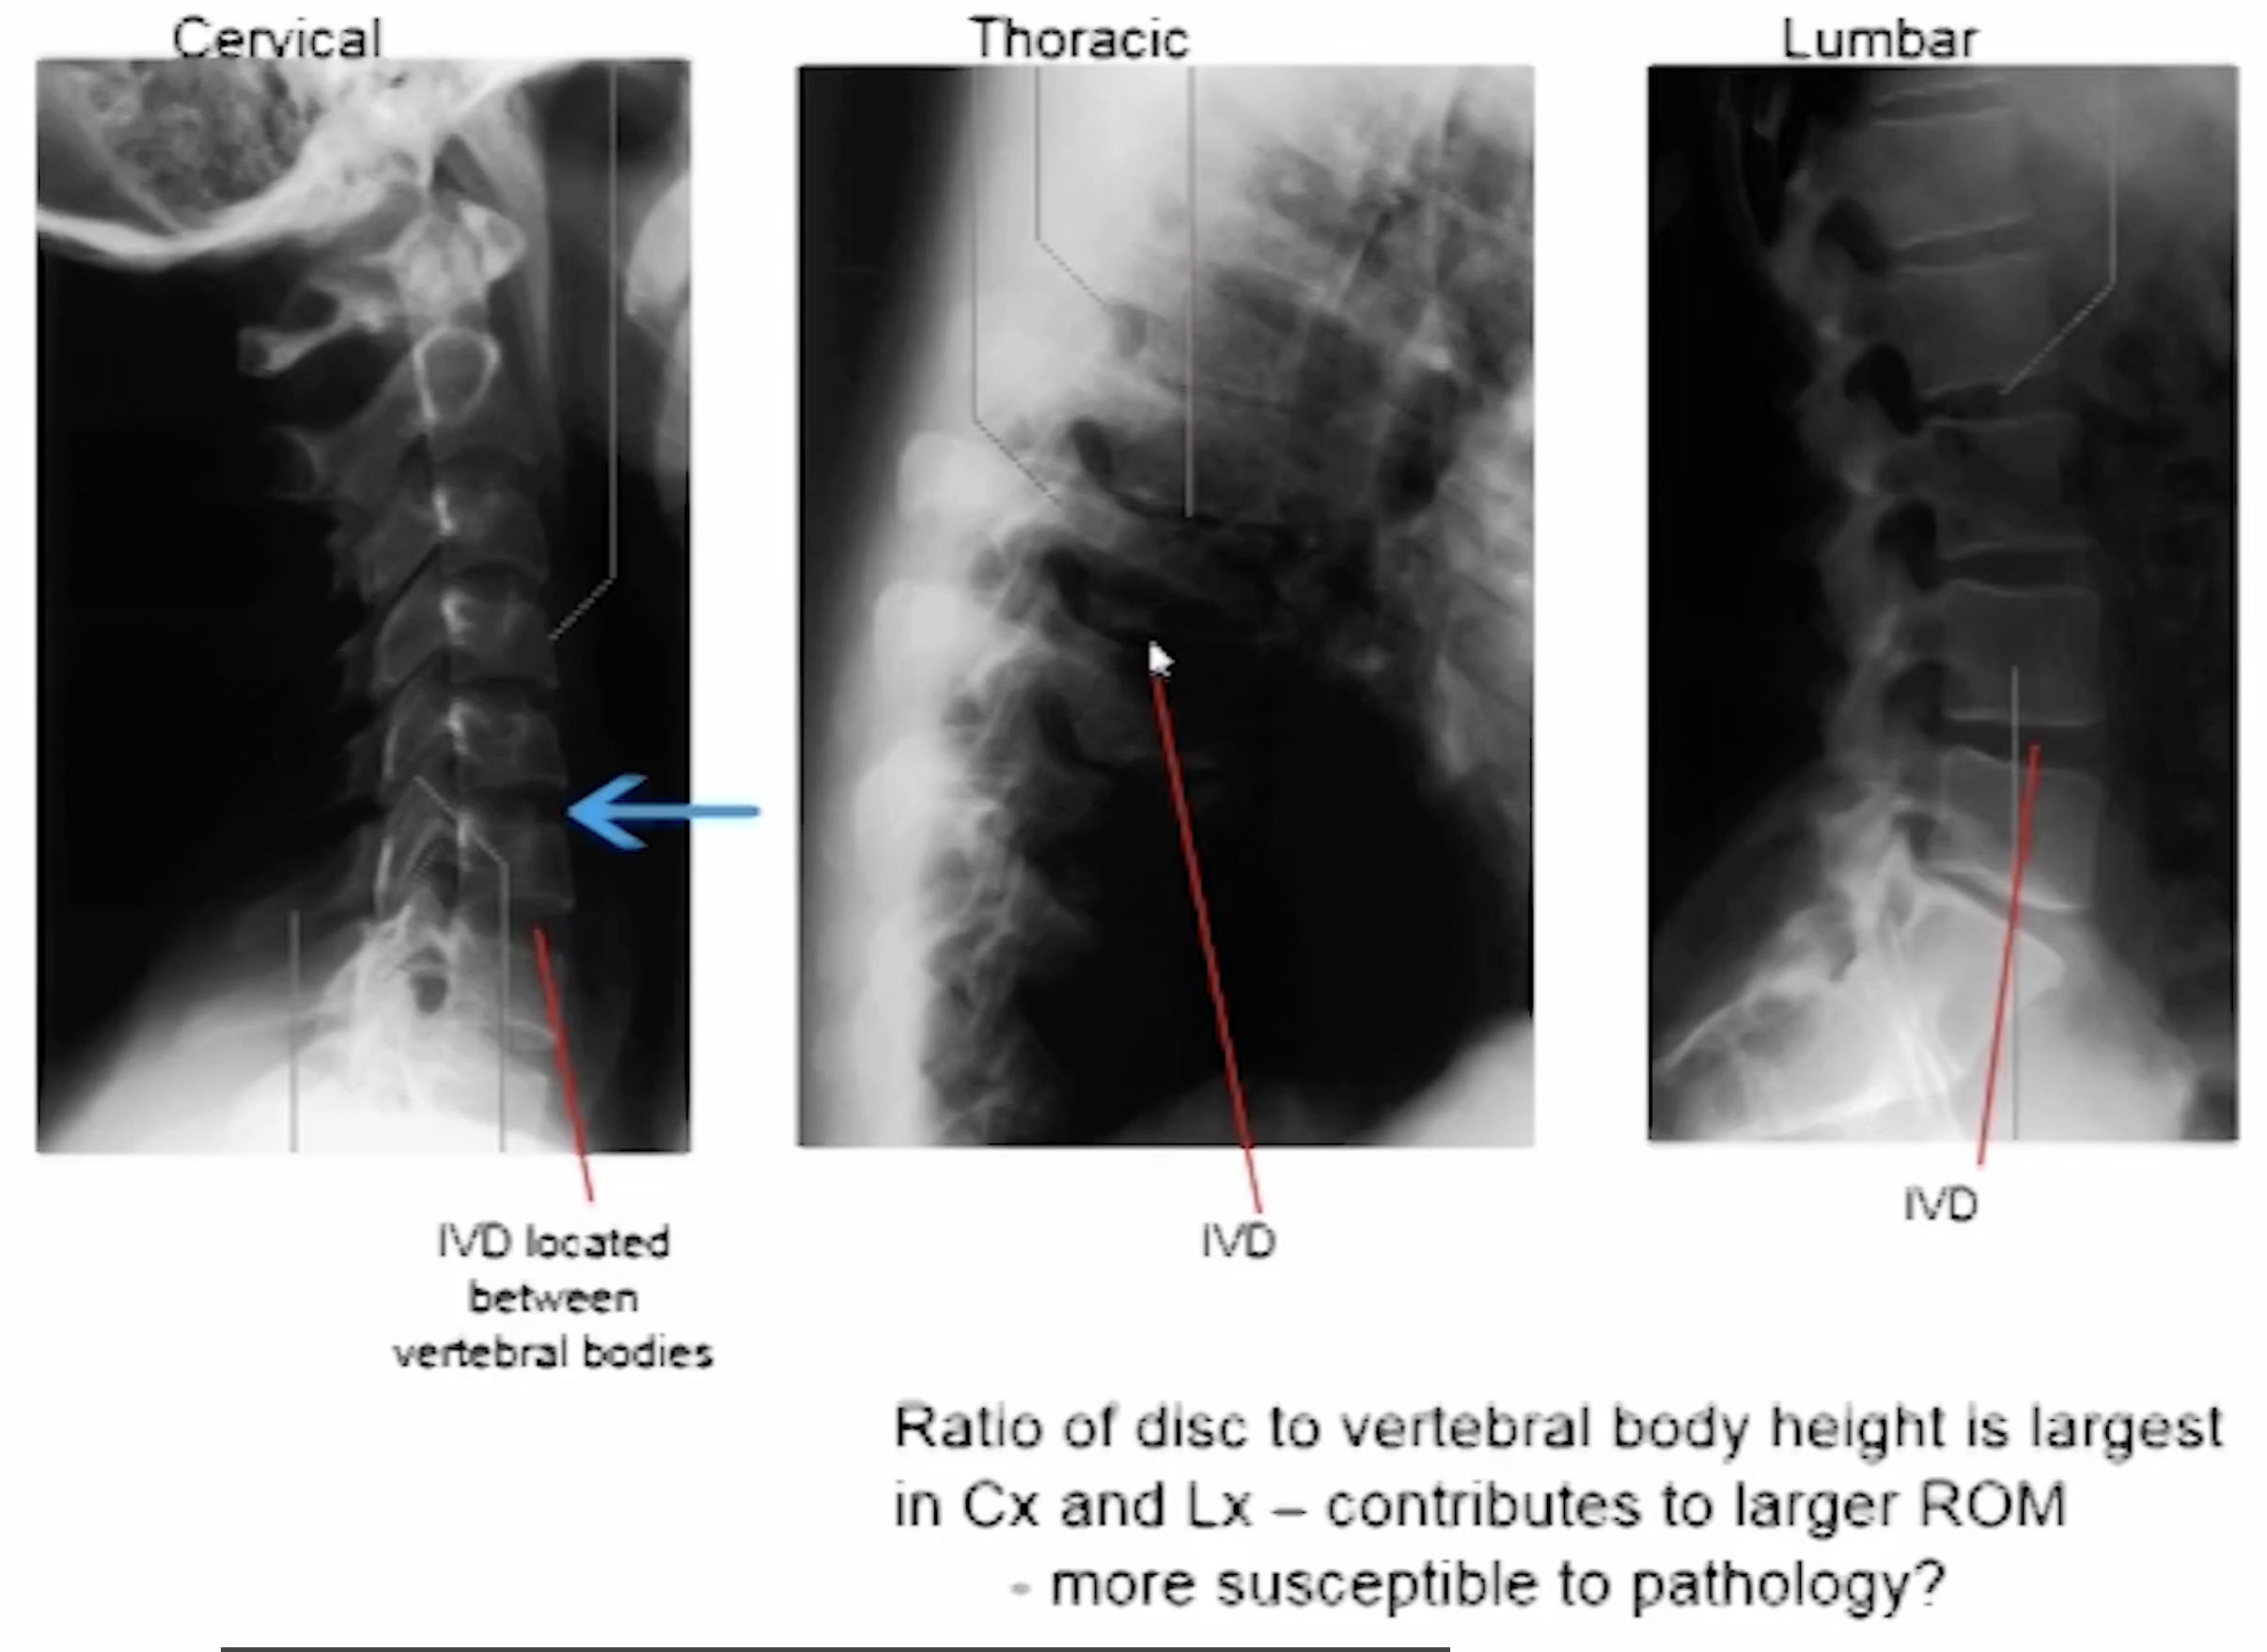

Means that part of the annulus fibrosis has been overstretched and damaged and the nucleus pulposus is able to push out. It often happens with flexion combined with rotation movements. Most common in cervical and lumbar regions because they have the greatest range of movement

When looking at an X-ray where would you see the IVD disc?

It is the black space between vertebral bodies